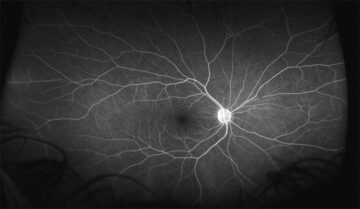

超広角走査レーザー検眼鏡 optos で網膜全体の出血や新生血管の分布を確認します。また進行度によっては血管造影検査も施行します。

- 超広角走査レーザー検眼鏡 optos:広範囲の出血・新生血管の把握